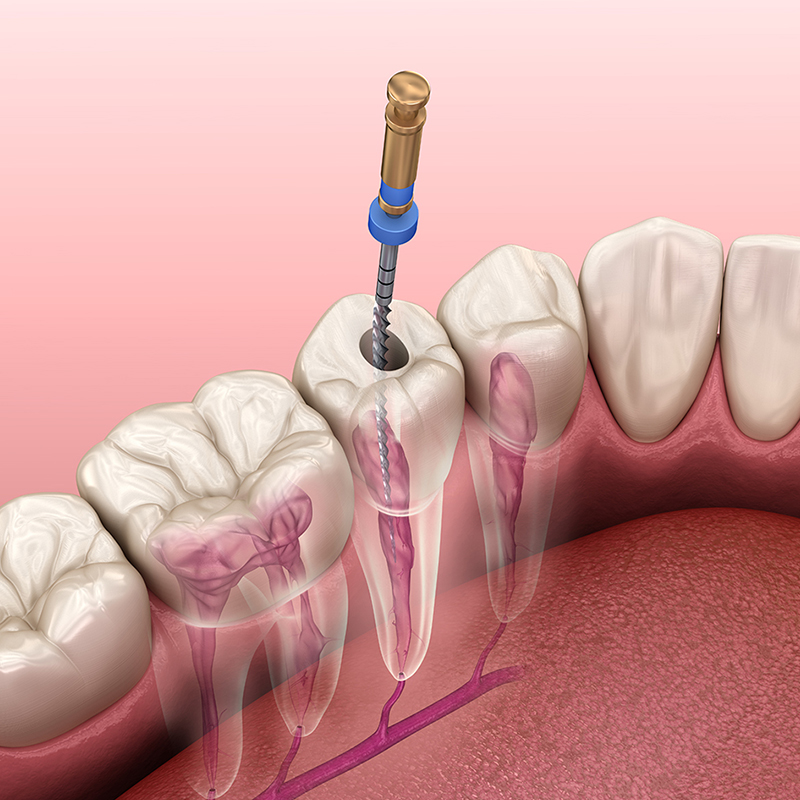

Procedura de endodontie este cunoscută și sub numele de “tratament de canal” și este realizată de obicei atunci când pulpa dentară este afectată grav. Procesul implică următoarele etape:

- Diagnosticul precis: Prin intermediul examenelor radiologice și a evaluării clinice, medicul dentist identifică prezența infecției sau inflamației în canalul radicular.

- Tratamentul canalului radicular: Procedura presupune îndepărtarea țesutului pulpar afectat, curățarea și sterilizarea canalului radicular și umplerea acestuia cu un material special pentru a preveni reinfecția.

- Restaurarea dintelui: După tratamentul de canal, dinte se restaurează pentru a-i reda funcționalitatea și aspectul natural. De obicei, se aplică o coroană dentară pentru protecție și rezistență suplimentară.